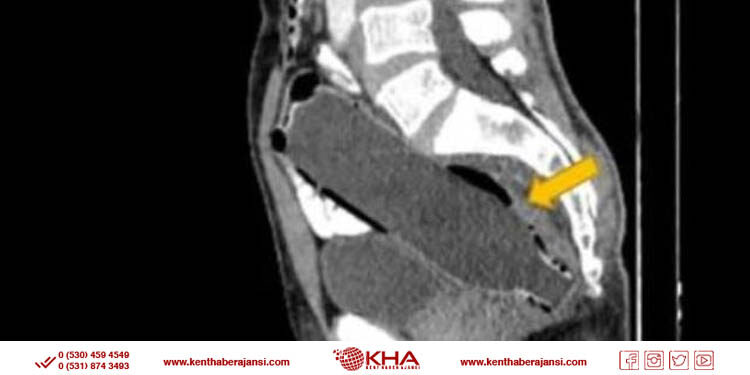

Doktorlar, adamın röntgen sonuçlarını incelemesinin ardından, hastanın makatında 12 santimetre boyunda pet şişe tespit etti. Daha sonra pet şişeyi adamın kendiliğinden makatına aldığı fakat karısından utandığı için durumu açıklayamadığı ve yapılan ameliyat ile şişe, makat bölgesi yırtılmadan ve kanama olmadan başarılı şekilde çıkarıldığı öğrenildi.